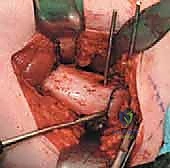

2. الفتح الجراحي والوصول للعظم

يتم عمل شق جراحي دقيق في الجزء الجانبي العلوي من الفخذ (المنطقة القريبة من الورك). يتم إبعاد العضلات برفق شديد للحفاظ على الأنسجة الرخوة والتروية الدموية للعظم، للوصول إلى منطقة "ما بين المدورين" (Intertrochanteric region).

4. القطع العظمي (The Osteotomy)

باستخدام منشار جراحي دقيق جداً وعالي السرعة، يتم إجراء قطع عرضي في عظم الفخذ في المنطقة المحددة. هذه الخطوة تفصل الجزء العلوي (الرأس والعنق) عن الجزء السفلي (جسم العظم).